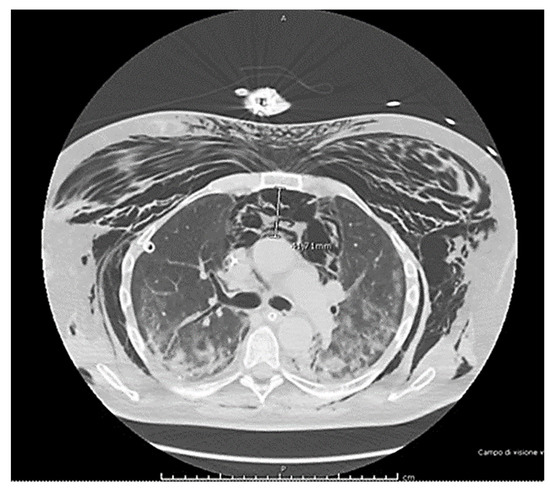

2. Case Presentation